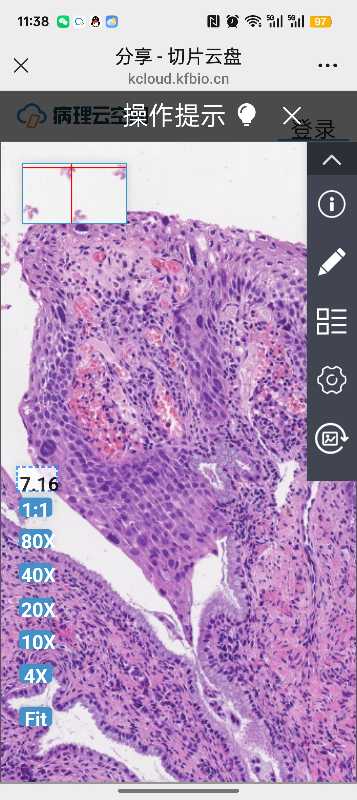

性别

女

年龄

57

临床诊断

宫颈病变

一般病史

体检

标本名称

宫颈活检

大体所见

软组织2块

hpv16+,求老师们帮忙看看是HSIL2-3吗

考虑为子宫颈高级别鳞状上皮内瘤变HSIL(CIN2-3级)

高级别CIN3